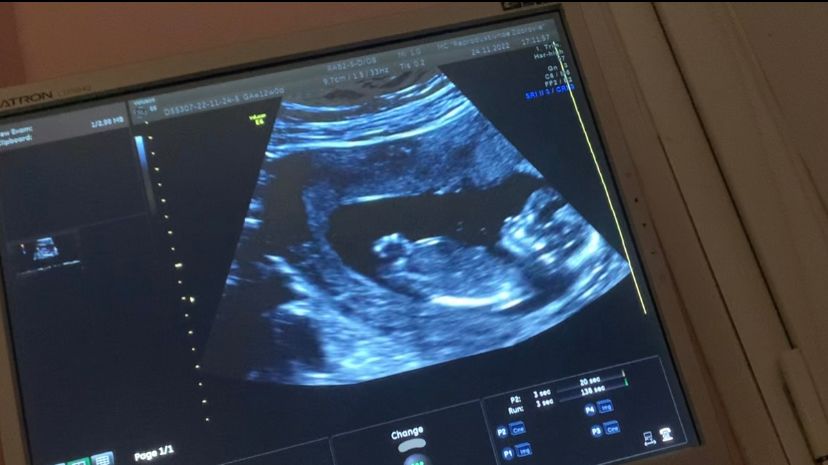

Потом зашли с мужем в кабинет, началось узи. Вижу своего малыша на экране, как он там развлекается и на сердце становится легче) Очень активный, крутился, вертелся, кувыркался, доктор с датчиком только успевал за ним)))

Итог - все у нас хорошо, развивается как положено, риски минимальные. Сказали следить за давлением(повышается риск преэклампсии к 37 неделе) и человек низковато прикрепился, но если его ничем не провоцировать, то и не страшно.

Пол - на 80% мальчик)

И по скринингу мы все таки больше на неделю из-за ранней овуляции.Так что 14 неделька уже пошла)